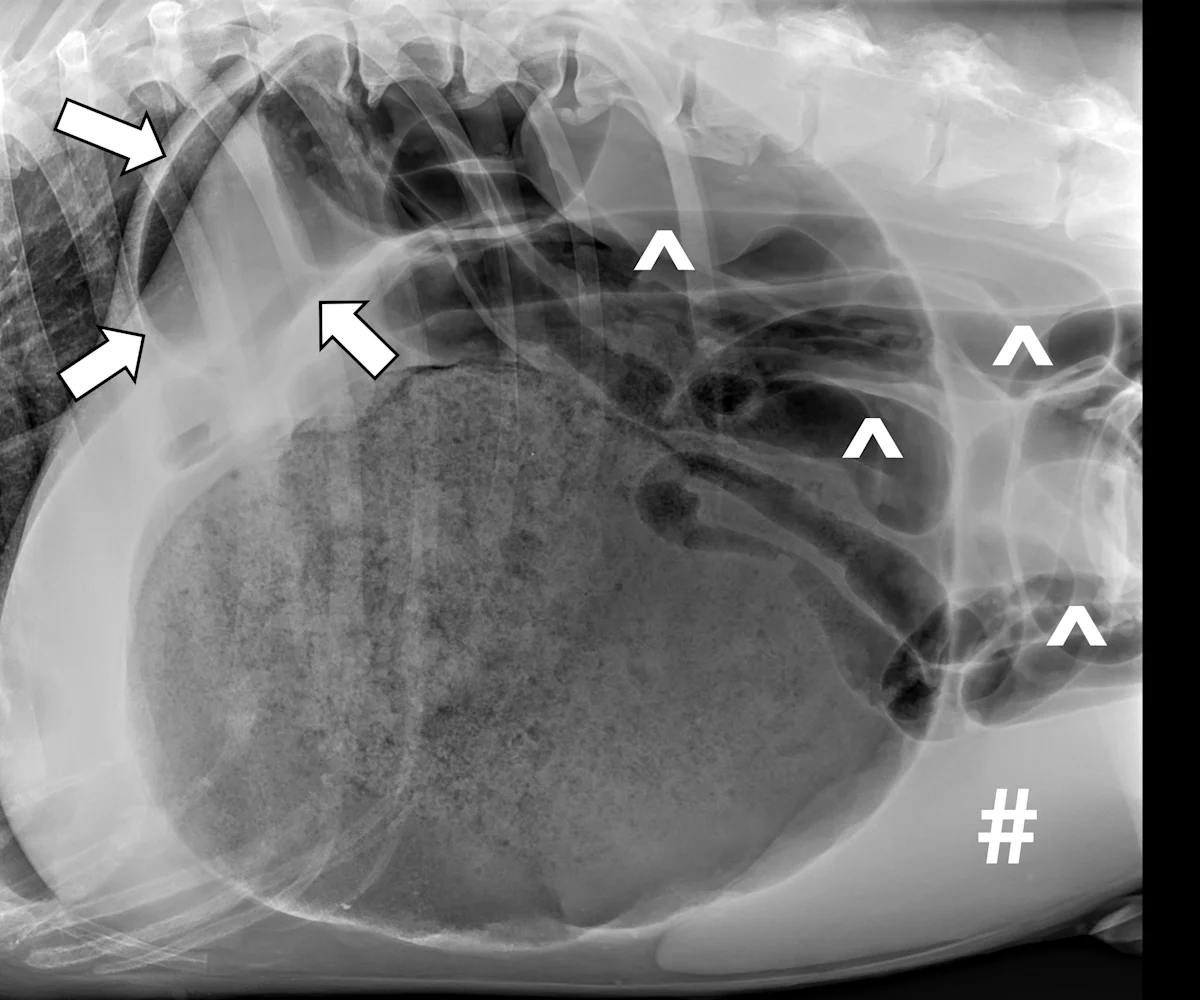

FIGURE 1

Right lateral radiograph of a dog with 180-GDV. Severe gastric dilatation with a craniodorsally displaced pylorus (arrows) is creating compartmentalization of the stomach. Diffuse small intestinal dilation (carets) and splenomegaly (pound sign) can also be seen.